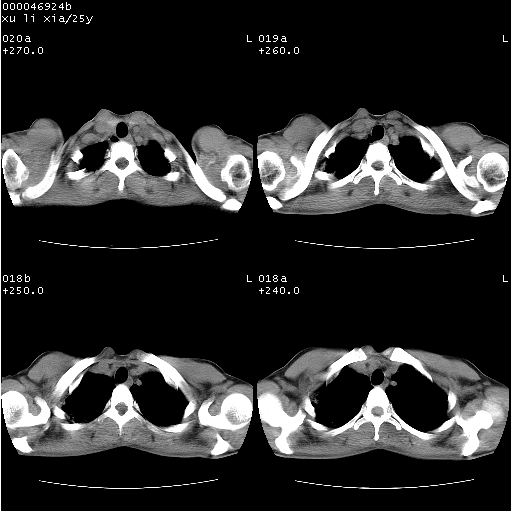

患者 女,25岁。因“左侧卵巢肿瘤”术前胸片偶然发现两肺病变。平素无明显不适,无呼吸系统症状及体征,无传染病史。

胸部ct轴位平扫(层厚10mm,螺距1.5,重建间隔10mm),图像如下:

病灶呈地图样分布于肺外围,与正常组织分界清晰+弥漫性磨玻璃影中见小叶间隔增厚呈碎石路样表现+年轻女性,无明显临床症状=肺泡蛋白沉积症?

双肺上叶可见节段性渗出性病变,可见树芽征像,左肺下叶背段可见结节影。

病灶呈离心性分布,以两上肺多见,远离肺血管纹理,有部分肺间质条索影,病人症状轻微,考虑结节病。

平行于间质走行微结节影;拌钙化灶;分布通气好的肺野